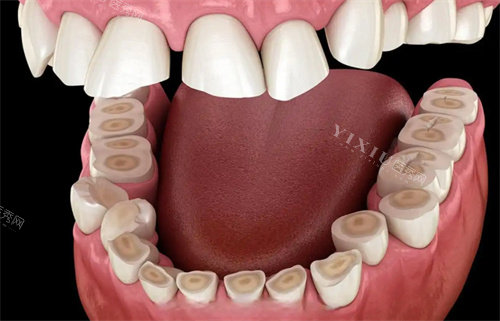

牙冠项目

金属烤瓷牙冠:650 元起

全瓷牙冠:2000 元起

二氧化锆牙冠:3000 元起

贵金属牙冠:4000 元起

钴铬合金牙冠:1500 元起

钛合金牙冠:2500 元起

玻璃陶瓷牙冠:3500 元起

氧化铝牙冠:1800 元起

树脂牙冠:1000 元起

高透氧化锆牙冠:5800 元起

牙冠材质不同,价格也有区别。贵金属和高透氧化锆牙冠生物相容性好、美观度高,价格较贵;金属烤瓷牙冠和树脂牙冠价格相对亲民。